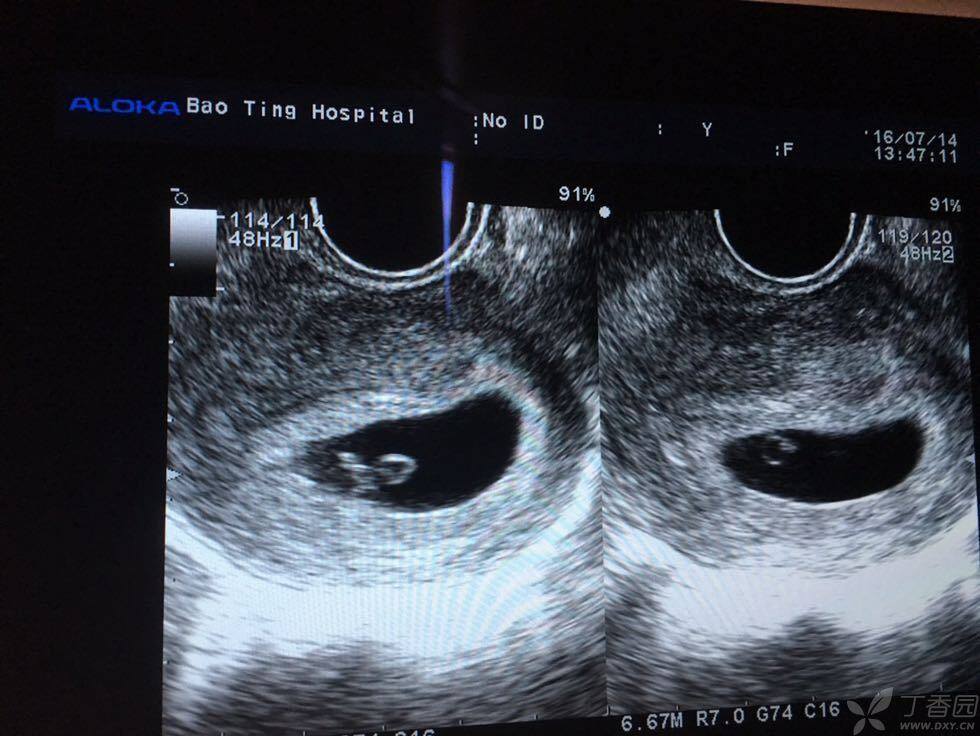

是否可以诊断早期双胎? [病例帖]

如一个孕囊内有两个卵黄囊及两个胚芽,则为单卵双胎附:早期妊娠天数及

报告上写着是一个孕囊,但是图上确有两个小东西,同事朋友都说不像是